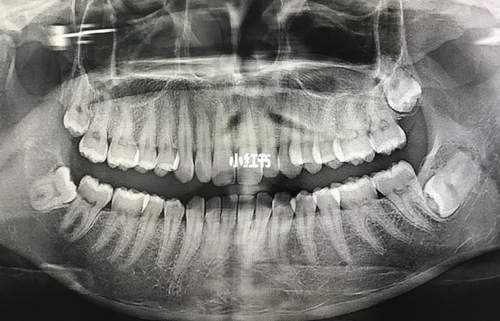

因为智齿是很特殊的牙齿,它的牙根是很深的,而且还特别复杂。所以说拔智齿一定要去正规的医院,找专业的牙科医生进行拔除。拔智齿前都会先拍片,会根据智齿的牙根在什么位置,再进行拔除。拔智齿前也要注意消炎,不能有炎症,消炎过后才能把智齿。智齿没有长全,但是已经影响到其它牙齿,就一定要拔掉,以免疼痛加重。